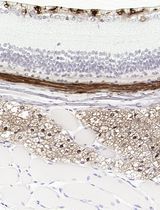

采用 Davidson 固定液和黑色素漂白法优化小鼠眼组织切片的免疫组化染色

Anne Nathalie Longakit [...] Catherine D. Van Raamsdonk

2025年11月20日 1562 阅读